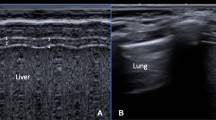

Using a recently published standardized technique [12, 19, 21,22,23,24,25], the right hemidiaphragm was assessed with the infant in a relaxed state facilitated by modified swaddling and occasionally pacifier administered by a second person. For DE measurements, the probe was placed subcostal between the anterior axillary and midclavicular line with a curvilinear probe using a standardized protocol for image acquisition. DE was measured as the difference in the position of the outer line of the diaphragm in M-mode at peak inspiration and expiration (Fig. 1a). DT was measured at the zone of apposition where thickening and shortening of the diaphragm could be appropriately evaluated. DT was obtained by placing the linear transducer at the 9th or 10th intercostal space near the mid-axillary line while the transducer was perpendicular to the chest wall [23, 24]. By B-mode, the diaphragm was identified as the hypo-echoic area (muscular layer) bordered by two echogenic lines of the diaphragmatic pleura (upper line) and peritoneum (lower line). Using M-mode tracing, the end of expiratory and inspiratory DT was calculated by determining the maximum perpendicular distance between the pleural and peritoneal layers, measuring only the distance of the hypoechoic area (Fig. 1b). To assess the efficiency of the diaphragm as a pressure generator, the DTF was determined [25]. DTF was calculated as the change in DTexp DTins using the following formula:

For each diaphragm parameter (DTexp, DTins, DTF, and DE), the average from at least three respiratory cycles was reported to reduce the risk of over or underestimating the diaphragmatic measurements [26]. Standard neonatal LU views, three chest areas on each side (upper anterior, lower anterior and lateral) were obtained, and LUS using grading score (ranges from 0–18 points) were determined as previously described [27, 28].

Lung ultrasound patterns and scoring: Lung ultrasound findings were categorized into 4 patterns 1 A-lines pattern (score = 0) indicates presence of A-lines artifact, pleural line sliding, and less than 3 B-lines; 2 Nonconfluent B-lines pattern (interstitial syndrome, score = 1), indicates more than 3 B-lines, and pleural line sliding; 3 Confluent B-lines pattern (white lung pattern, score = 2) indicates confluent B-lines, and pleural line sliding; 4 consolidation pattern (subpleural consolidation > 5 mm, score = 3) with absent A-lines, confluent B lines